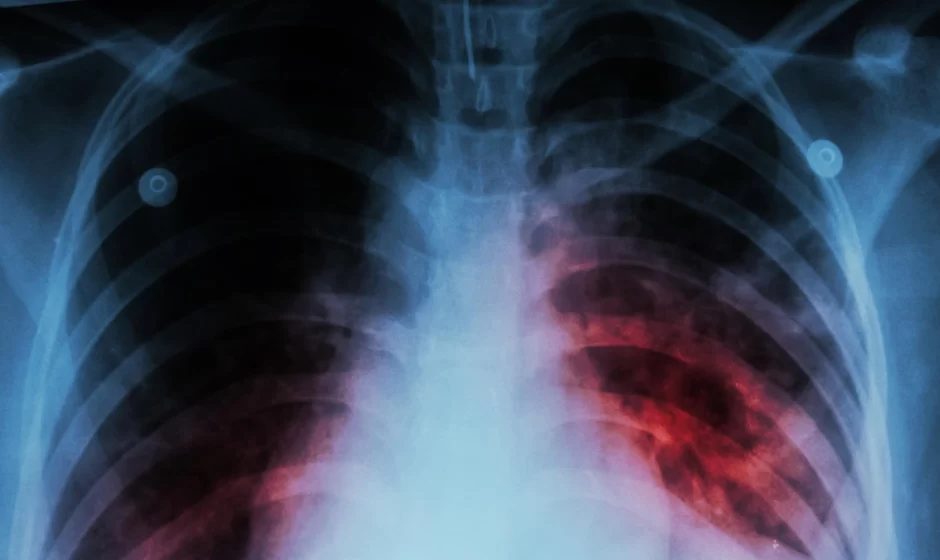

Repuntan casos de tuberculosis respiratoria en México durante inicio de 2026

Mientras la atención sanitaria nacional se ha concentrado en el reciente brote de sarampión, la tuberculosis respiratoria muestra un incremento significativo en México durante las primeras semanas de 2026, de acuerdo con datos oficiales de la Secretaría de Salud.

La tuberculosis respiratoria es una enfermedad infecciosa causada por la bacteria Mycobacterium tuberculosis. Aunque es prevenible y curable, las autoridades sanitarias subrayan la importancia de su detección oportuna y del apego estricto al tratamiento médico.

Entre los principales síntomas se encuentran tos persistente, en ocasiones con flema o sangre; fiebre; pérdida de peso; fatiga y sudoración excesiva, especialmente durante la noche. El tratamiento consiste en el uso de antibióticos por un periodo mínimo de seis meses, y su interrupción sin supervisión médica puede provocar resistencia a los medicamentos.